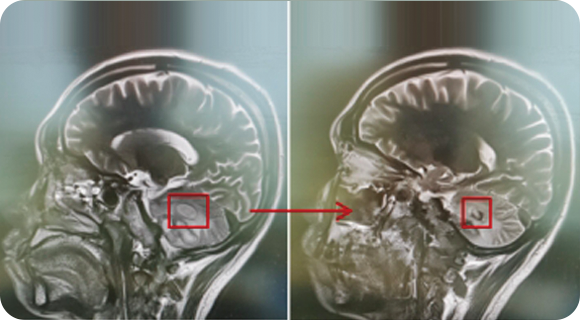

从事神经外科工作30年,擅长脑与脊髓血管类疾病、肿瘤、外伤等疾病的诊断与治疗,尤其擅长神经介入治疗各类脑血管疾病。累计完成介入栓塞颅内动脉瘤2000多例,颅内血管畸形数百例,夹闭颅内动脉瘤数百例,手术颅内与脊髓肿瘤数百例。在脑和脊髓血管病、肿瘤、外伤等方面有丰富的经验和较深造诣。

精通颅内动脉瘤介入栓塞和手术夹闭双技术,系统掌握脑动静脉畸形、颈内动脉海绵窦漏、硬脑膜动静脉漏等颅内血管疾病的诊疗和手术,精通颈动脉、椎动脉狭窄的血管内重建技术,以及颈动脉狭窄的内膜剥脱手术技术。在颅内肿瘤、椎管内肿瘤、颅脑损伤、高血压脑出血等疾病的诊治和手术,脑功能性疾病立体定向手术治疗等方面也积累了丰富的经验。

擅长脑血管病(出血与缺血)的神经介入与微创手术,能熟练开展脑外伤、重度颅脑损伤的救治工作。